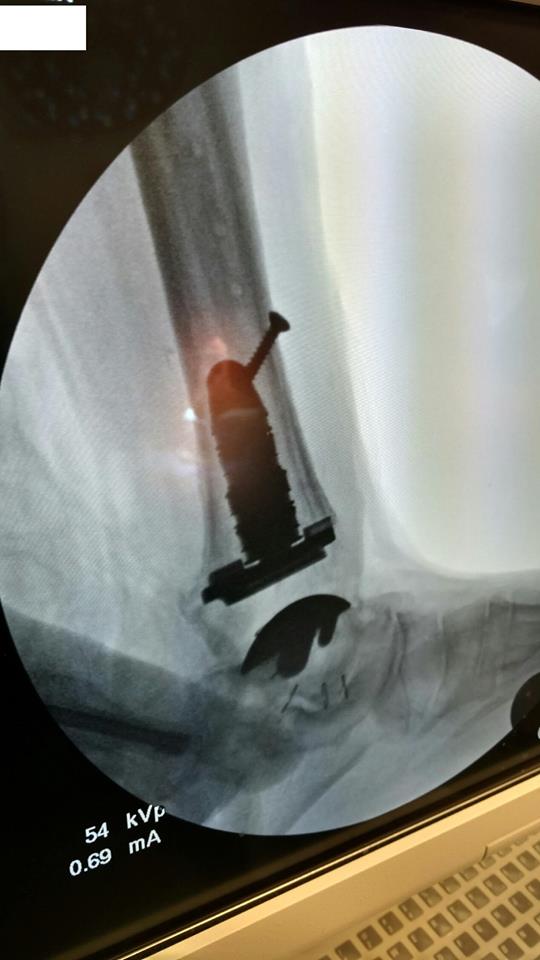

"Surgical misadventure" by another surgeon about 8 years ago. The wrong fixation was used for a flatfoot repair, & the deformity was not corrected. Patient came in with severe foot & ankle pain, with no arch at all. She was unable to play with her grandchild because the pain was so bad, & because she felt unsteady. The old hardware was removed, a lateral calcaneal lengthening osteotomy was performed along with a medial column/1st ray realignment. The ankle was painfully arthritic, & patient elected a total ankle replacement vs. an ankle fusion. She is now able to walk pain free & play with her grandchildren!

Ten years of severe ankle pain with a mal-positioned ankle fusion is now relieved! Patient is now walking with pain-free ankle motion!